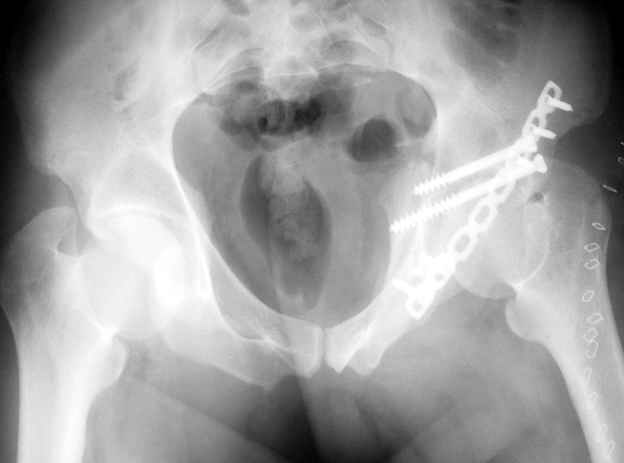

Высылаю пример еще одного случая, остеосинтез пластиной из подвздошного доступа.